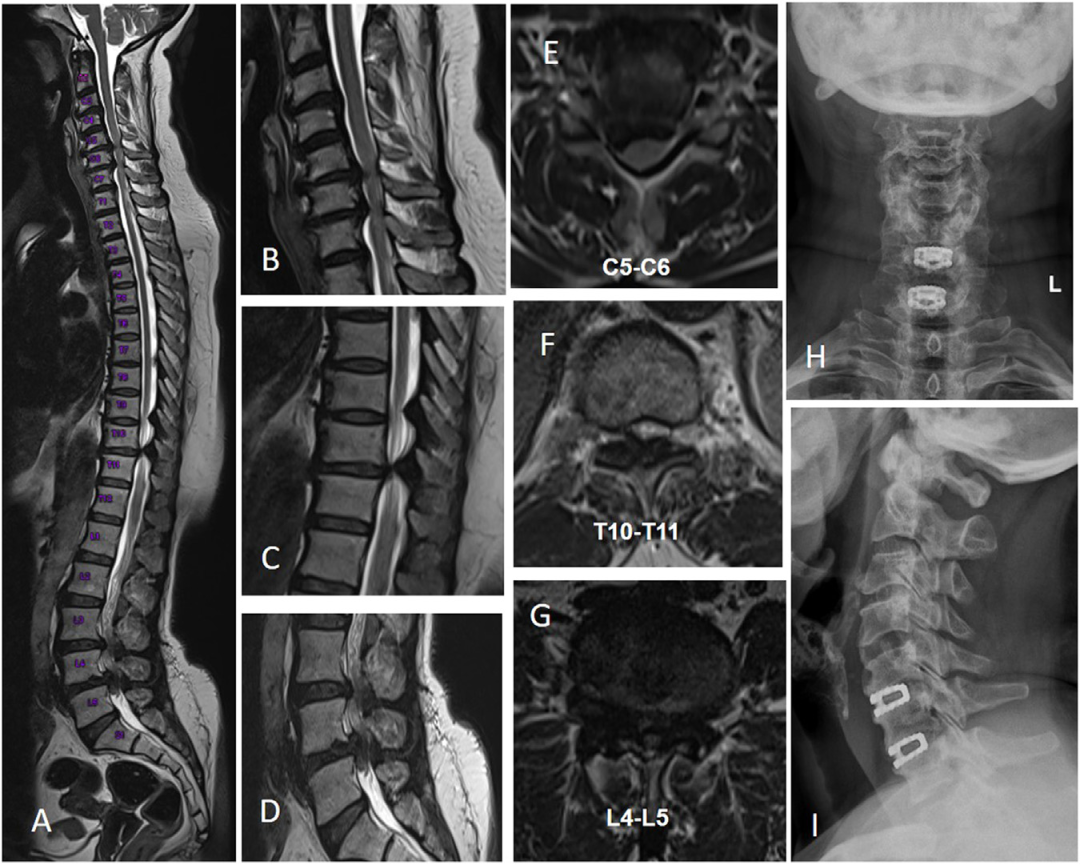

C型:胸腰型,TL-TSS,分为2个亚型。

C1型-存在下肢脊髓病症状。

C2型-仅出现腰椎症状而无脊髓病的患者。

C1型有6例(30%)需要另行腰椎手术;而C2型没有患者需要另行胸椎手术。